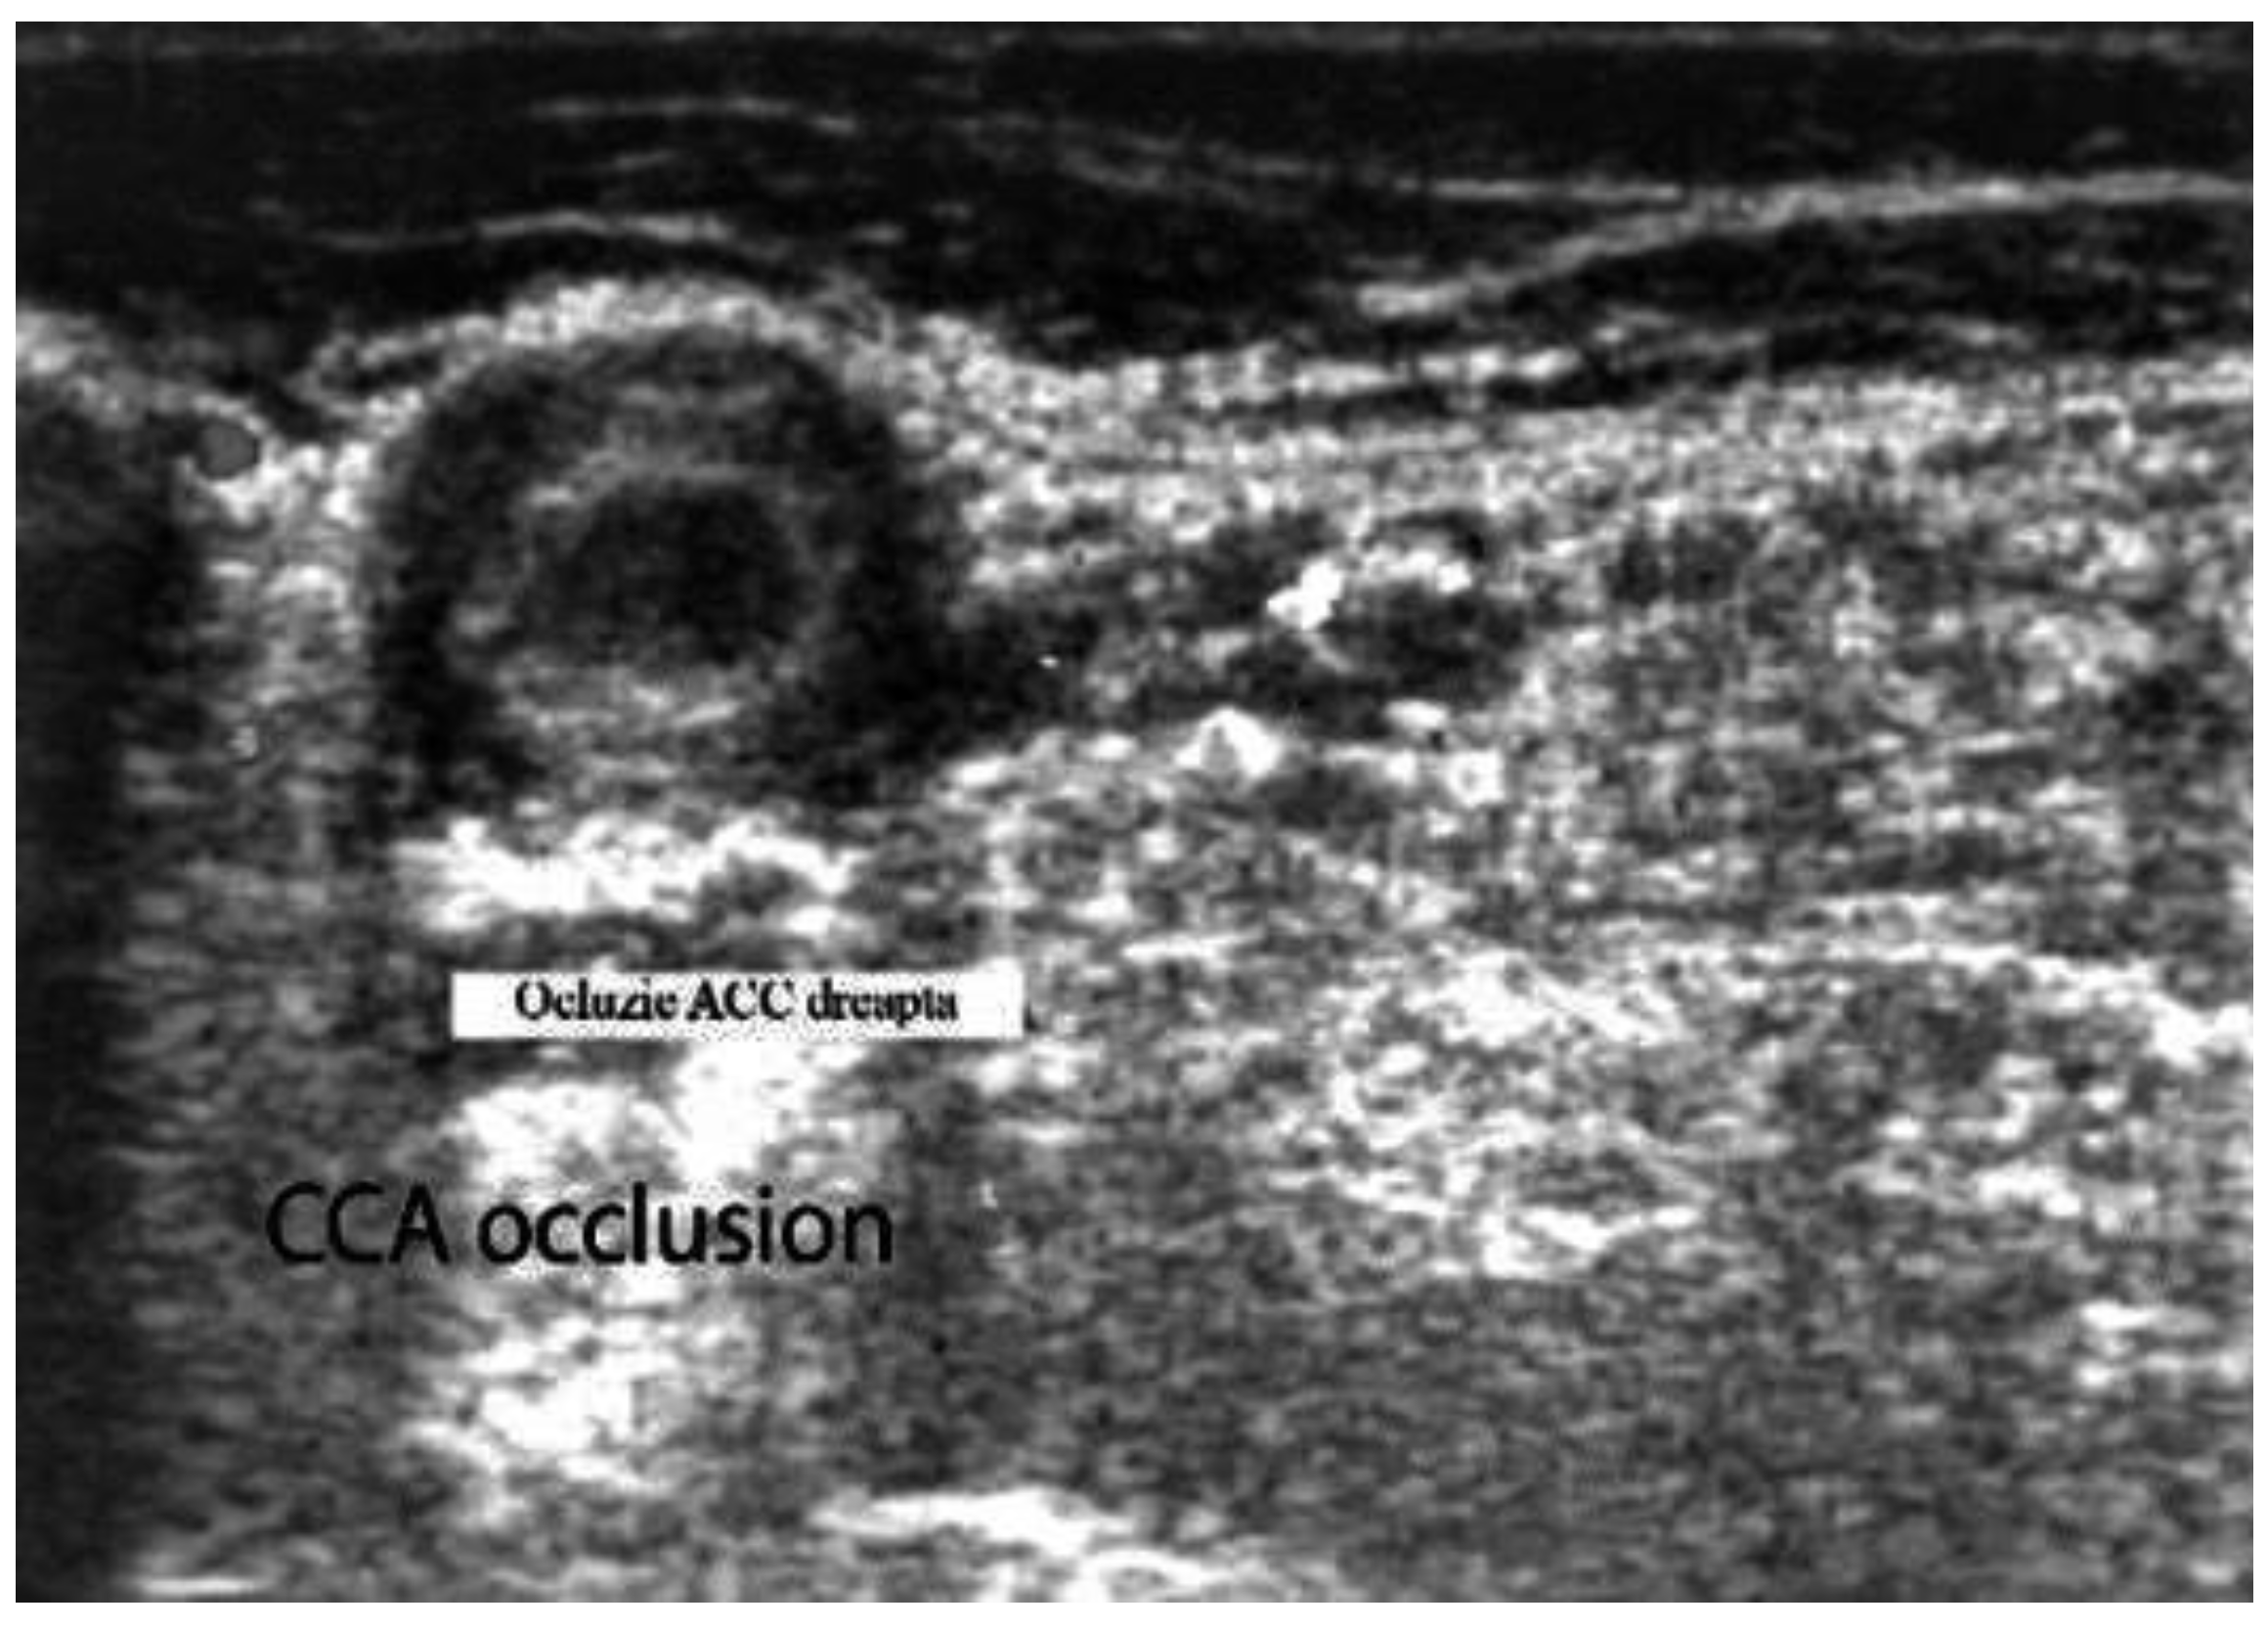

- Acute occlusions, wherein the US image is similar to that of acute embolism in different other vessels, with lack of color Doppler signals (even with low pulse repetition frequency and high color gain) in a visible artery lumen filled with hypoechoic material (cloth) [30,31,32,33,34,35,36,37,38,39,40,41].

- Large size arteries: the common carotid arteries (CCAs), the ECAs, the internal carotid arteries (ICA’s), the vertebral, the subclavian, and the axillary arteries,